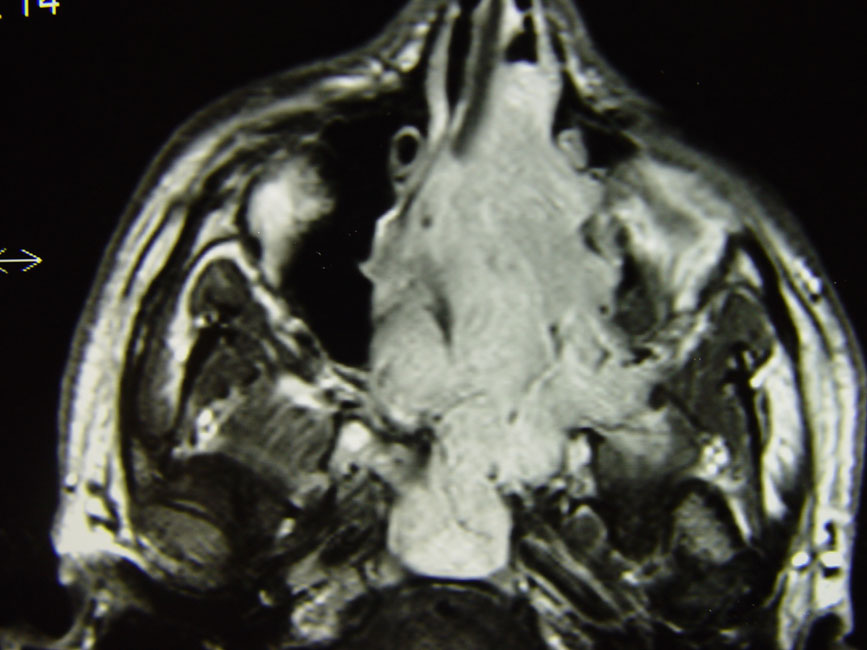

Μαγνητική τομογραφία όγκου της μύτης που επεκτείνεται στους παρακείμενους παραρρινίους κόλπους.

Κλείνοντας τις αιτίες της ρινικής απόφραξης δεν θα πρέπει να παραλείψουμε και την πιθανότητα ανάπτυξης όγκου. Συνήθως πρόκειται για απόφραξη που εξελίσσεται ταχέως είναι συνήθως μονόπλευρη και συχνά συνοδεύεται από ρινορραγίες. Η εξέταση της μύτης με ενδοσκόπιο θα αποκαλύψει τον όγκο το είδος του οποίου θα προσδιορισθεί με βιοψία , ενώ το μέγεθος και οι σχέσεις του, με αξονική ή μαγνητική τομογραφία.